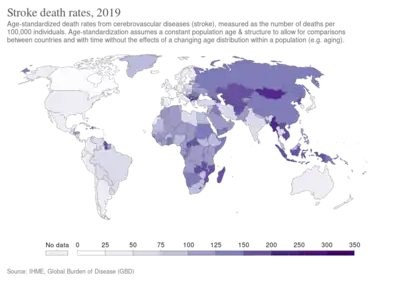

Epidemiology

|

no data

<250

250–425

425–600

600–775

775–950

950–1125

|

1125–1300

1300–1475

1475–1650

1650–1825

1825–2000

>2000

|

Stroke was the second most frequent cause of death worldwide in 2011, accounting for 6.2 million deaths (~11% of the total).[213] Approximately 17 million people had a stroke in 2010 and 33 million people have previously had a stroke and were still alive.[17] Between 1990 and 2010 the number of strokes decreased by approximately 10% in the developed world and increased by 10% in the developing world.[17] Overall, two-thirds of strokes occurred in those over 65 years old.[17] South Asians are at particularly high risk of stroke, accounting for 40% of global stroke deaths.[214]

It is ranked after heart disease and before cancer.[2] In the United States stroke is a leading cause of disability, and recently declined from the third leading to the fourth leading cause of death.[215] Geographic disparities in stroke incidence have been observed, including the existence of a "stroke belt" in the southeastern United States, but causes of these disparities have not been explained.